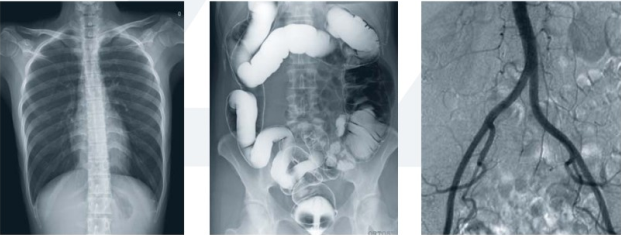

動(dòng)態(tài)DR的顯著特點(diǎn)是多項(xiàng)功能復(fù)合。隨著影像技術(shù)的快速發(fā)展,新一代DR不再是只能實(shí)現(xiàn)簡(jiǎn)單的拍片功能,而且擁有透視、造影等多項(xiàng)復(fù)合功能。

動(dòng)態(tài)DR擁有可視化造影功能,在進(jìn)行造影檢查時(shí),成像幅面大,無(wú)需移動(dòng)球管,一個(gè)幅面就可以連續(xù)觀看造影劑的流向以及造影部位的全部情況,在造影過(guò)程中還能實(shí)現(xiàn)900萬(wàn)像素實(shí)時(shí)點(diǎn)片,為醫(yī)生的臨床診斷提供優(yōu)異的影像數(shù)據(jù)。

動(dòng)態(tài)DR能實(shí)現(xiàn)全身拼接,適用于全脊柱、全下肢攝影,輔助脊柱畸形的矯形治療、康復(fù)檢查,為臨床提供高精度圖像。

動(dòng)態(tài)平板DR的透視和攝影均使用同一高效動(dòng)態(tài)平板,提供無(wú)與倫比的臨床應(yīng)用范圍,包括幾乎所有的普放檢查、胃腸鋇餐檢查和血管造影檢查等。

高效動(dòng)態(tài)平板在透視過(guò)程中可以達(dá)到每秒30幀,使動(dòng)態(tài)透視獲得媲美平板攝影的圖像質(zhì)量與尺寸,更有利于臨床診需求。

采用大尺寸動(dòng)態(tài)平板技術(shù),大范圍覆蓋檢查面積,對(duì)任何結(jié)構(gòu)部分進(jìn)行檢查時(shí),可提供比16英寸影像增強(qiáng)器多50%的覆蓋尺寸,是傳統(tǒng)影像增強(qiáng)器無(wú)可比擬的功能;同時(shí),透視檢查時(shí)不需要對(duì)病人重新定位便可觀察到足夠大的人體器官組織。